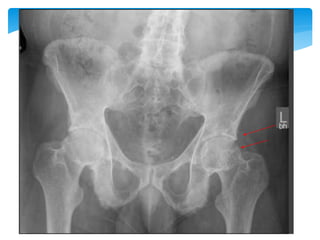

Sacroiliitis

0 Normal

1 Some blurring of the joint margins - suspicious

2 Minimal sclerosis with some erosions

3

Severe erosions with widening of joint space +/- some ankylosis

(Pseudo-widening of the joint space: Subchondral bone resorption—

blurring ; Erosion sclerosis ;Calcification leading to ankylosis)

4 complete ankylosis

Grade 0 Grade 1 Grade 3 Grade 4

20歲年輕女性,

HLAB27+

相隔四年的X光片